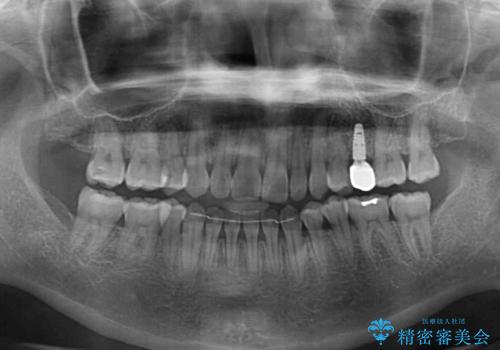

傾斜した下顎の奥歯は、矯正治療にてまずは歯軸を改善させ、隙間が閉じられるようであればそのままに、閉じられないようであればインプラント治療を行うこととしました。

上顎のむし歯の酷い残存乳歯は抜歯をし、矯正治療の途中でインプラントを埋入、矯正治療後に補綴治療を行うこととしました。

舌の突出癖改善のトレーニングが全くうまくできず、治療期間が長期化しました。

早く治療を終えたいとの要望があり、トレーニング次第と伝えるとようやく練習をするようになり、その後は速やかに上下の隙間が改善されました。